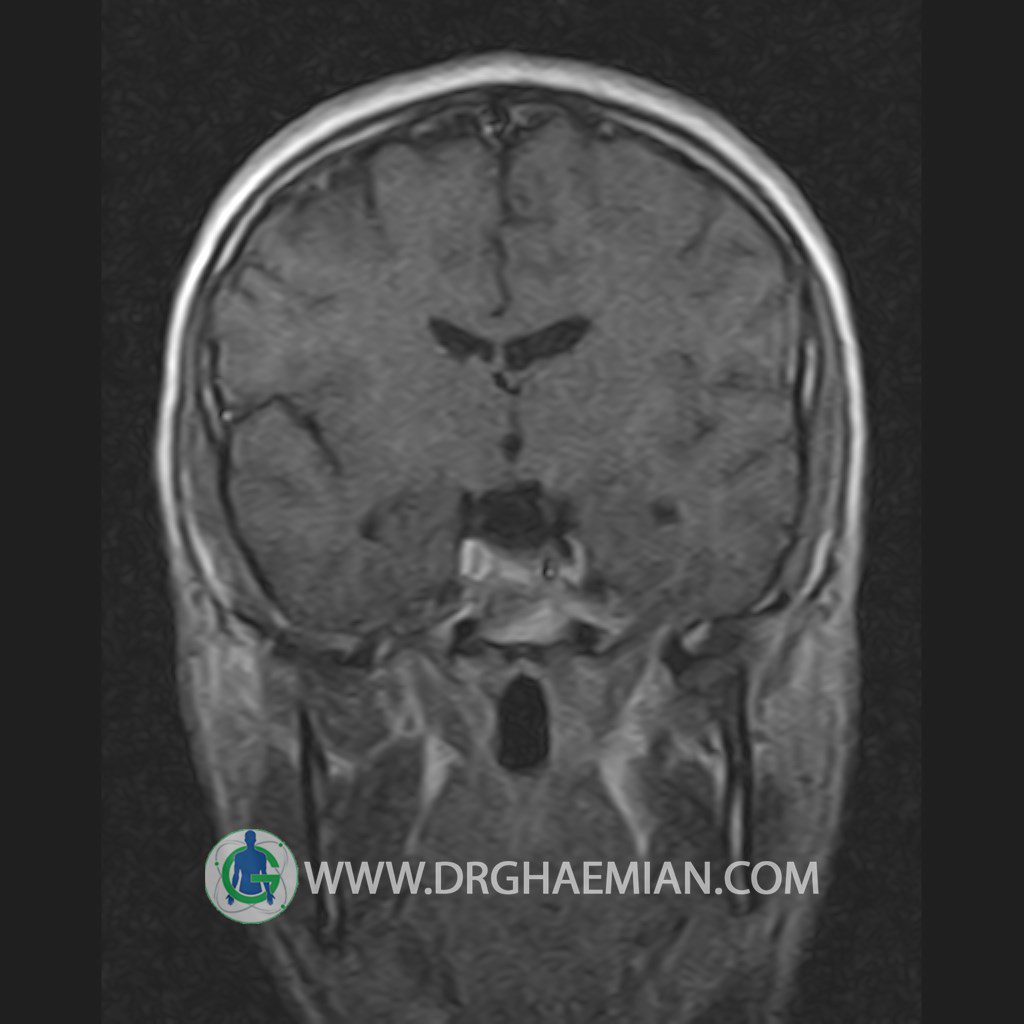

پزشکان اغلب از تصویربرداری ام آر آی برای تشخیص و درمان عارضه های پزشکی که فقط با استفاده از اشعه ایکس یا میدان مغناطیسی و امواج رادیویی قابل مشاهده است، استفاده می کنند. دستگاه ام آر آی تصاویر دقیق از ساختار های داخلی بدن ایجاد می کند. در این کیس یک میکروآدنوم در هیپوفیز بیمار مشاهده می شود.

HYPOPHYSIS MRI

(with and without contrast)

Technique: Axial , coronal T1 , Axial , coronal , sagittal T2 , Axial, coronal T1 post Gd & 64 dynamic thin coronal slices.

REPORT :

The infundibulum is centered and of normal size .

The optic chiasm and suprasellar spaces appear normal .

The cavernous sinus and imaged portions of the internal carotid artery and carotid siphon are unremarkable .

Evaluable portions of the neurocranium show no abnormalities .

The sphenoid sinus is clear and pneumatized .

Imaging of the hypothalamus after contrast medium administration was normal.

– Small hypoenhancing mass lesion ( 3 x 4 mm ) in posterior of pituitary stalk suggestive for micro adenoma

– Mucosal thickening in ethmoid & maxillary sinuses

is seen